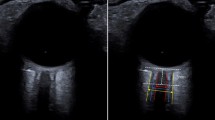

MRI in all individuals was performed using a 3T Magnetom Total Imaging Matrix Trio (Siemens Medical Solutions, Munich, Germany). The axial proton density/T2-weighted turbo spin-echo fat-suppressed sequence was used to measure ONSD and optic nerve diameter (OND). The scan parameters were as follows: repetition time 4,600 ms, echo time 12 ms, pixel bandwidth 185 Hz/pixel, slice thickness 4 mm, spacing between slices 5 mm, and number of slices 27. The optic nerve sheath appeared as a high signal surrounding a region of low signal corresponding to the optic nerve (Figure 1). The axial image slice that provided the best view of the ONSD was chosen and the slice was interpolated to 1,000 × 1,333 pixels using Image J 1.38 (National Institutes of Heath, Bethesda, MD, USA). The retrobulbar area was zoomed to 300×, and then ONSD and OND were measured in an axis perpendicular to the optic nerve, 3 mm behind the globe using an electronic caliper. The OND and the ONSD values obtained from both sides were averaged for comparison with ICP measurements.